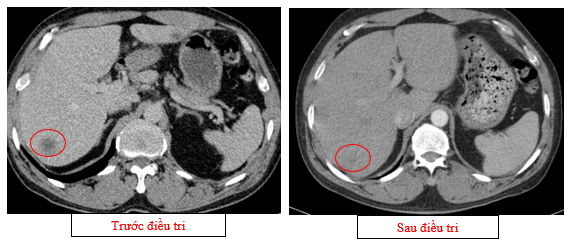

- Chụp cắt lớp vi tính ổ bụng (08/2025): Nhu mô gan phải có vài nốt, nốt lớn nhất hạ phân thùy VII có nốt giảm tỷ trọng, ngấm thuốc kém sau tiêm đường kính 24mm, hạ phân thùy II, III có nốt 2 giảm tỷ trọng đường kính 13mm và 27mm. Các ổ đặc xương rải rác đốt sống ngực thắt lưng, xương cùng và xương chậu hai bên – theo dõi tổn thương thứ phát

Hình 04: Nhu mô gan phải có vài nốt, nốt lớn nhất hạ phân thùy VII có nốt giảm tỷ trọng, ngấm thuốc kém sau tiêm đường kính 24mm, hạ phân thùy II, III có nốt 2 giảm tỷ trọng đường kính 13mm và 27mm

Hình 05: Các ổ đặc xương rải rác đốt sống ngực thắt lưng, xương cùng và xương chậu hai bên – theo dõi tổn thương thứ phát

- Chụp cắt lớp vi tính ổ bụng (11/2025): Nhu mô gan phải có vài nốt, nốt lớn nhất hạ phân thùy VII có nốt giảm tỷ trọng, ngấm thuốc kém sau tiêm đường kính 8mm, hạ phân thùy II, III có nốt giảm tỷ trọng đường kính (tổn thương giảm đáng kể so với phim chụp ngày 08/2025). Các ổ đặc xương rải rác đốt sống ngực thắt lưng, xương cùng và xương chậu hai bên

Hình 11: Tổn thương ngấm thuốc kém nhu mô gan hạ phân thùy II giảm đáng kể kích thước

Hình 12: Tổn thương ngấm thuốc kém nhu mô gan hạ phân thùy VII giảm đáng kể kích thước

- Các tổn thương ngấm thuốc kém do di căn tại gan giảm kích thước đáng kể (27mm còn 8mm)